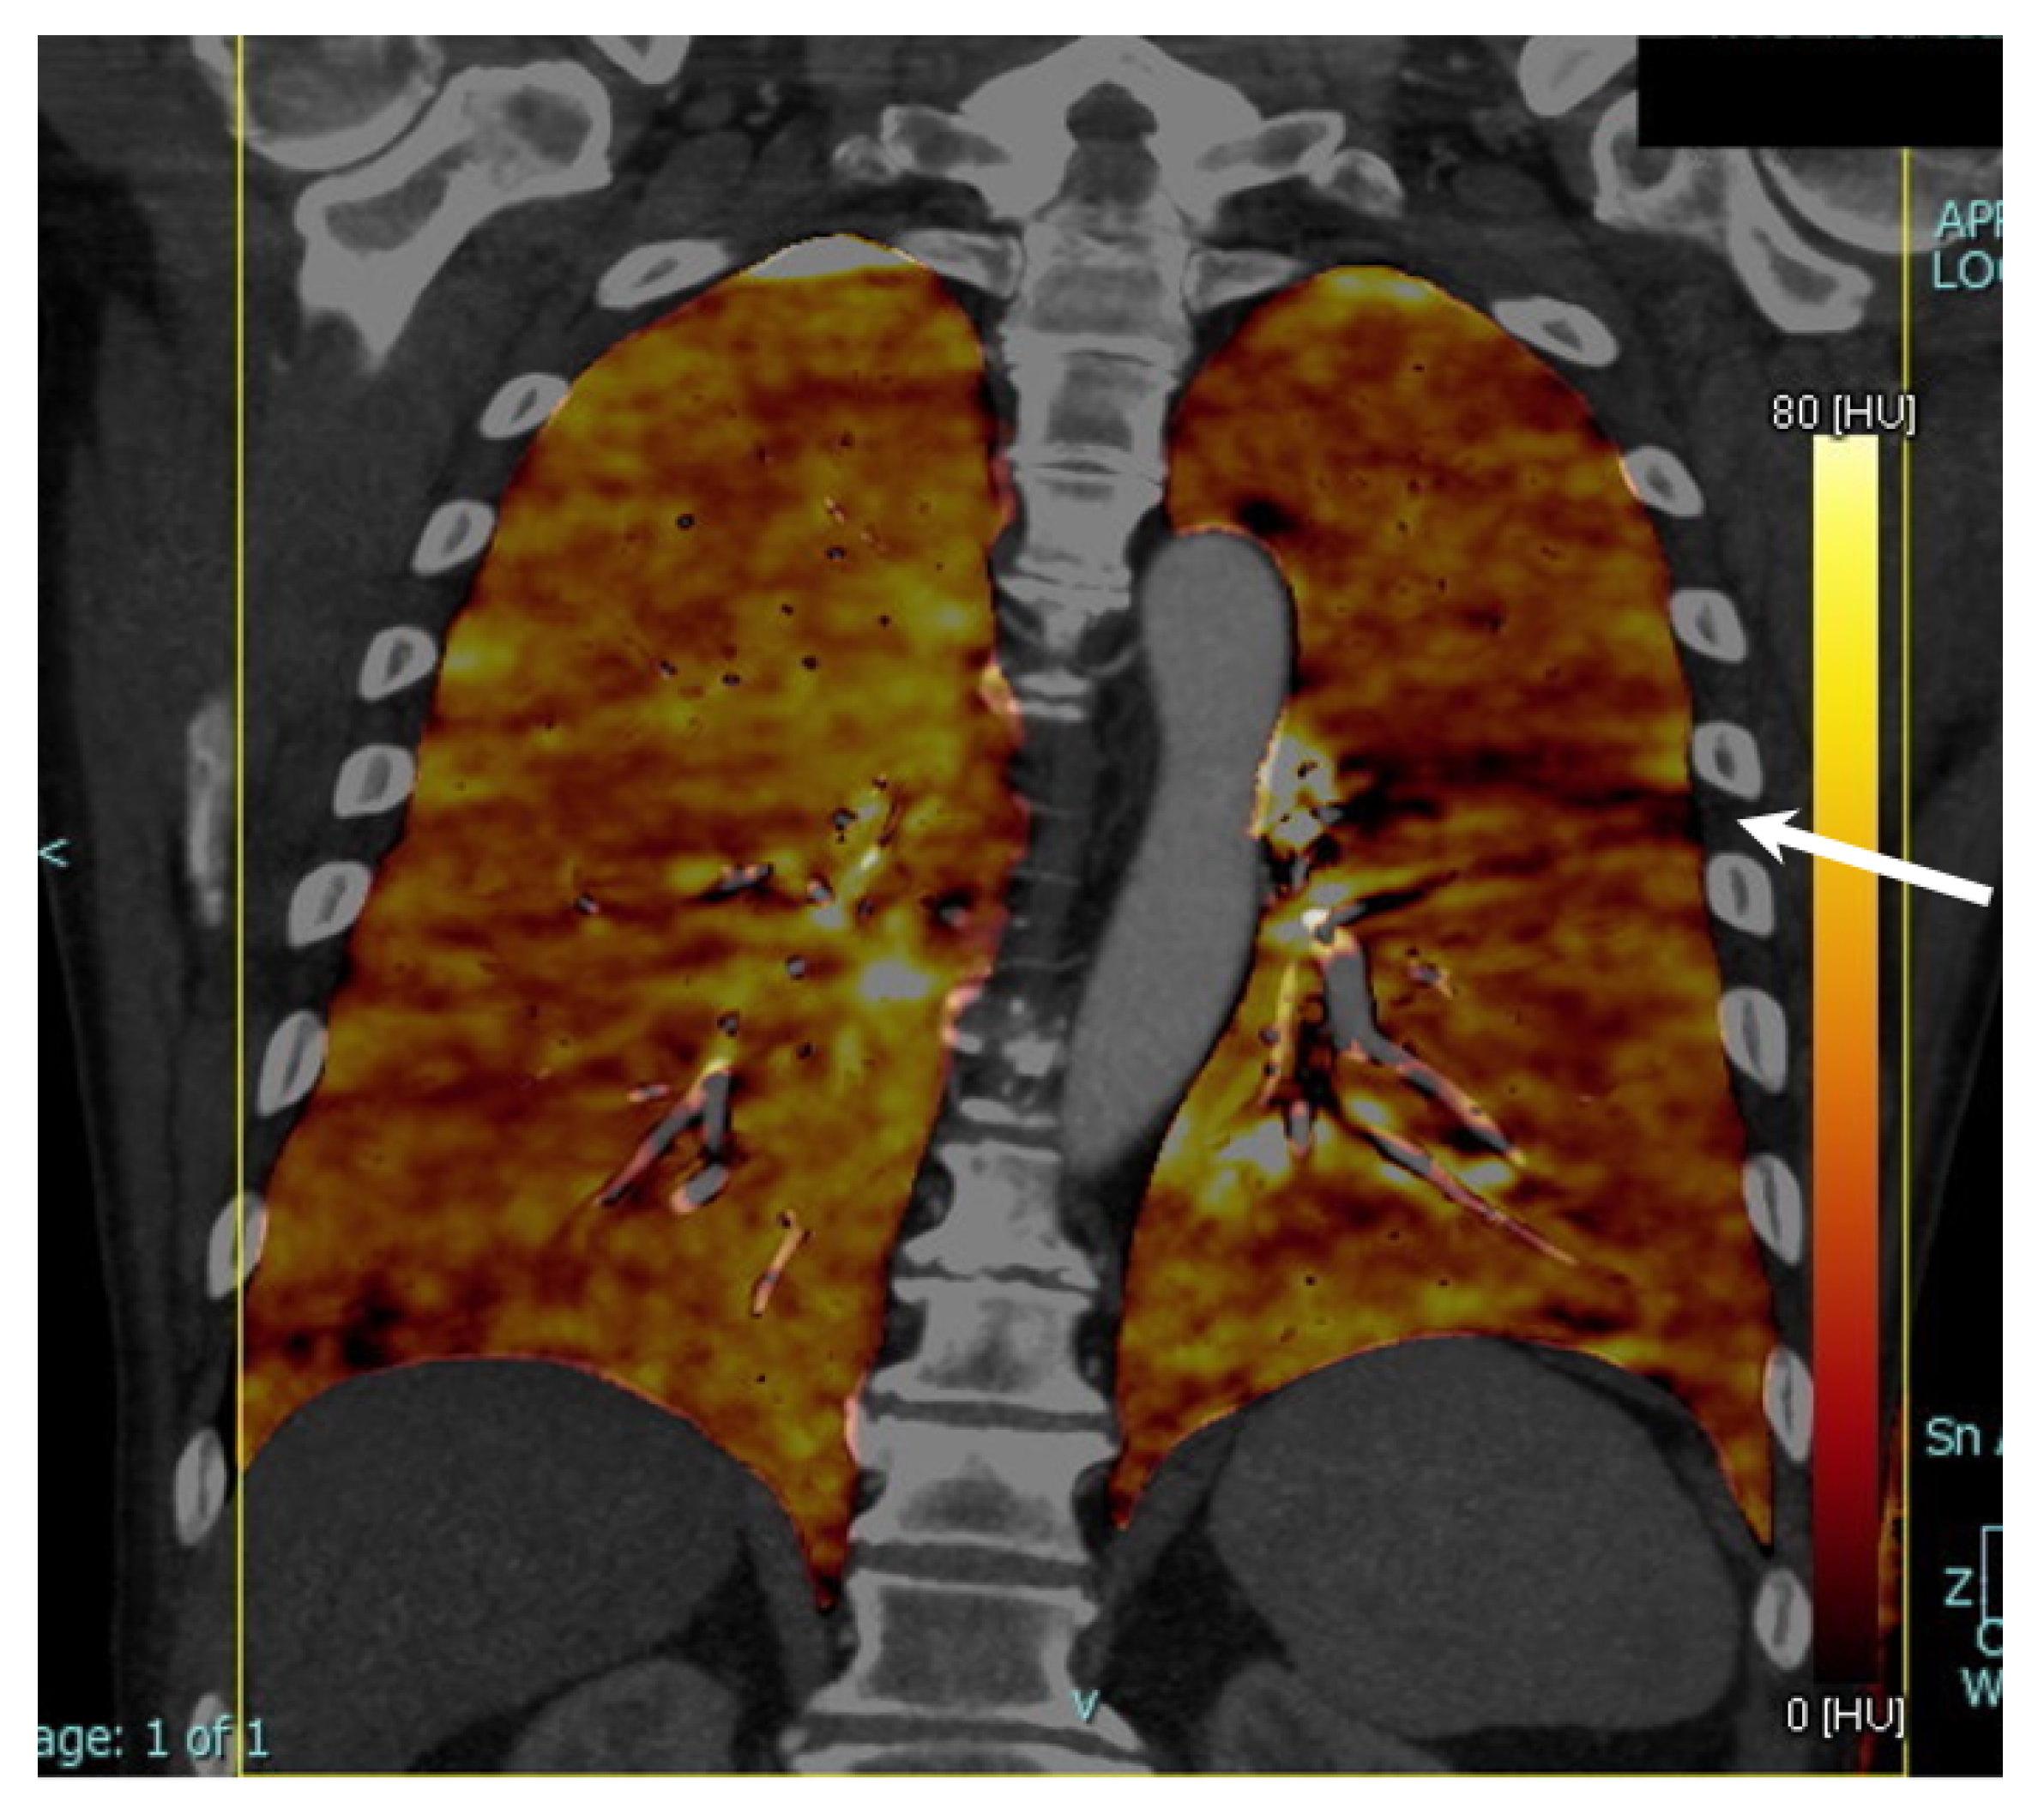

2.2. Imaging Acquisition

2.3. Imaging Post-Processing